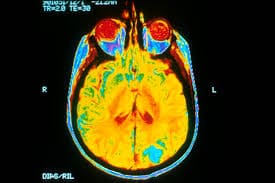

Brain Imaging Tests

For detecting memory degeneration, images of the brain can offer assistance. The images of the brain can specifically pinpoint visible anomalies related to the condition. The images also help detect cognitive changes in the brain.

Imaging Of Brain Structure

Magnetic Resonance Imaging (MRI)

A strong magnetic field and radio waves can produce detailed images to detect any problems. The sophisticated images may not provide information on the status of memory degeneration. But, it can rule out other conditions causing similar symptoms.